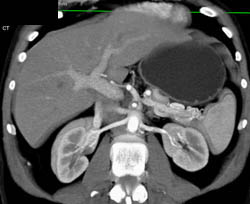

Hemangioma in 3D